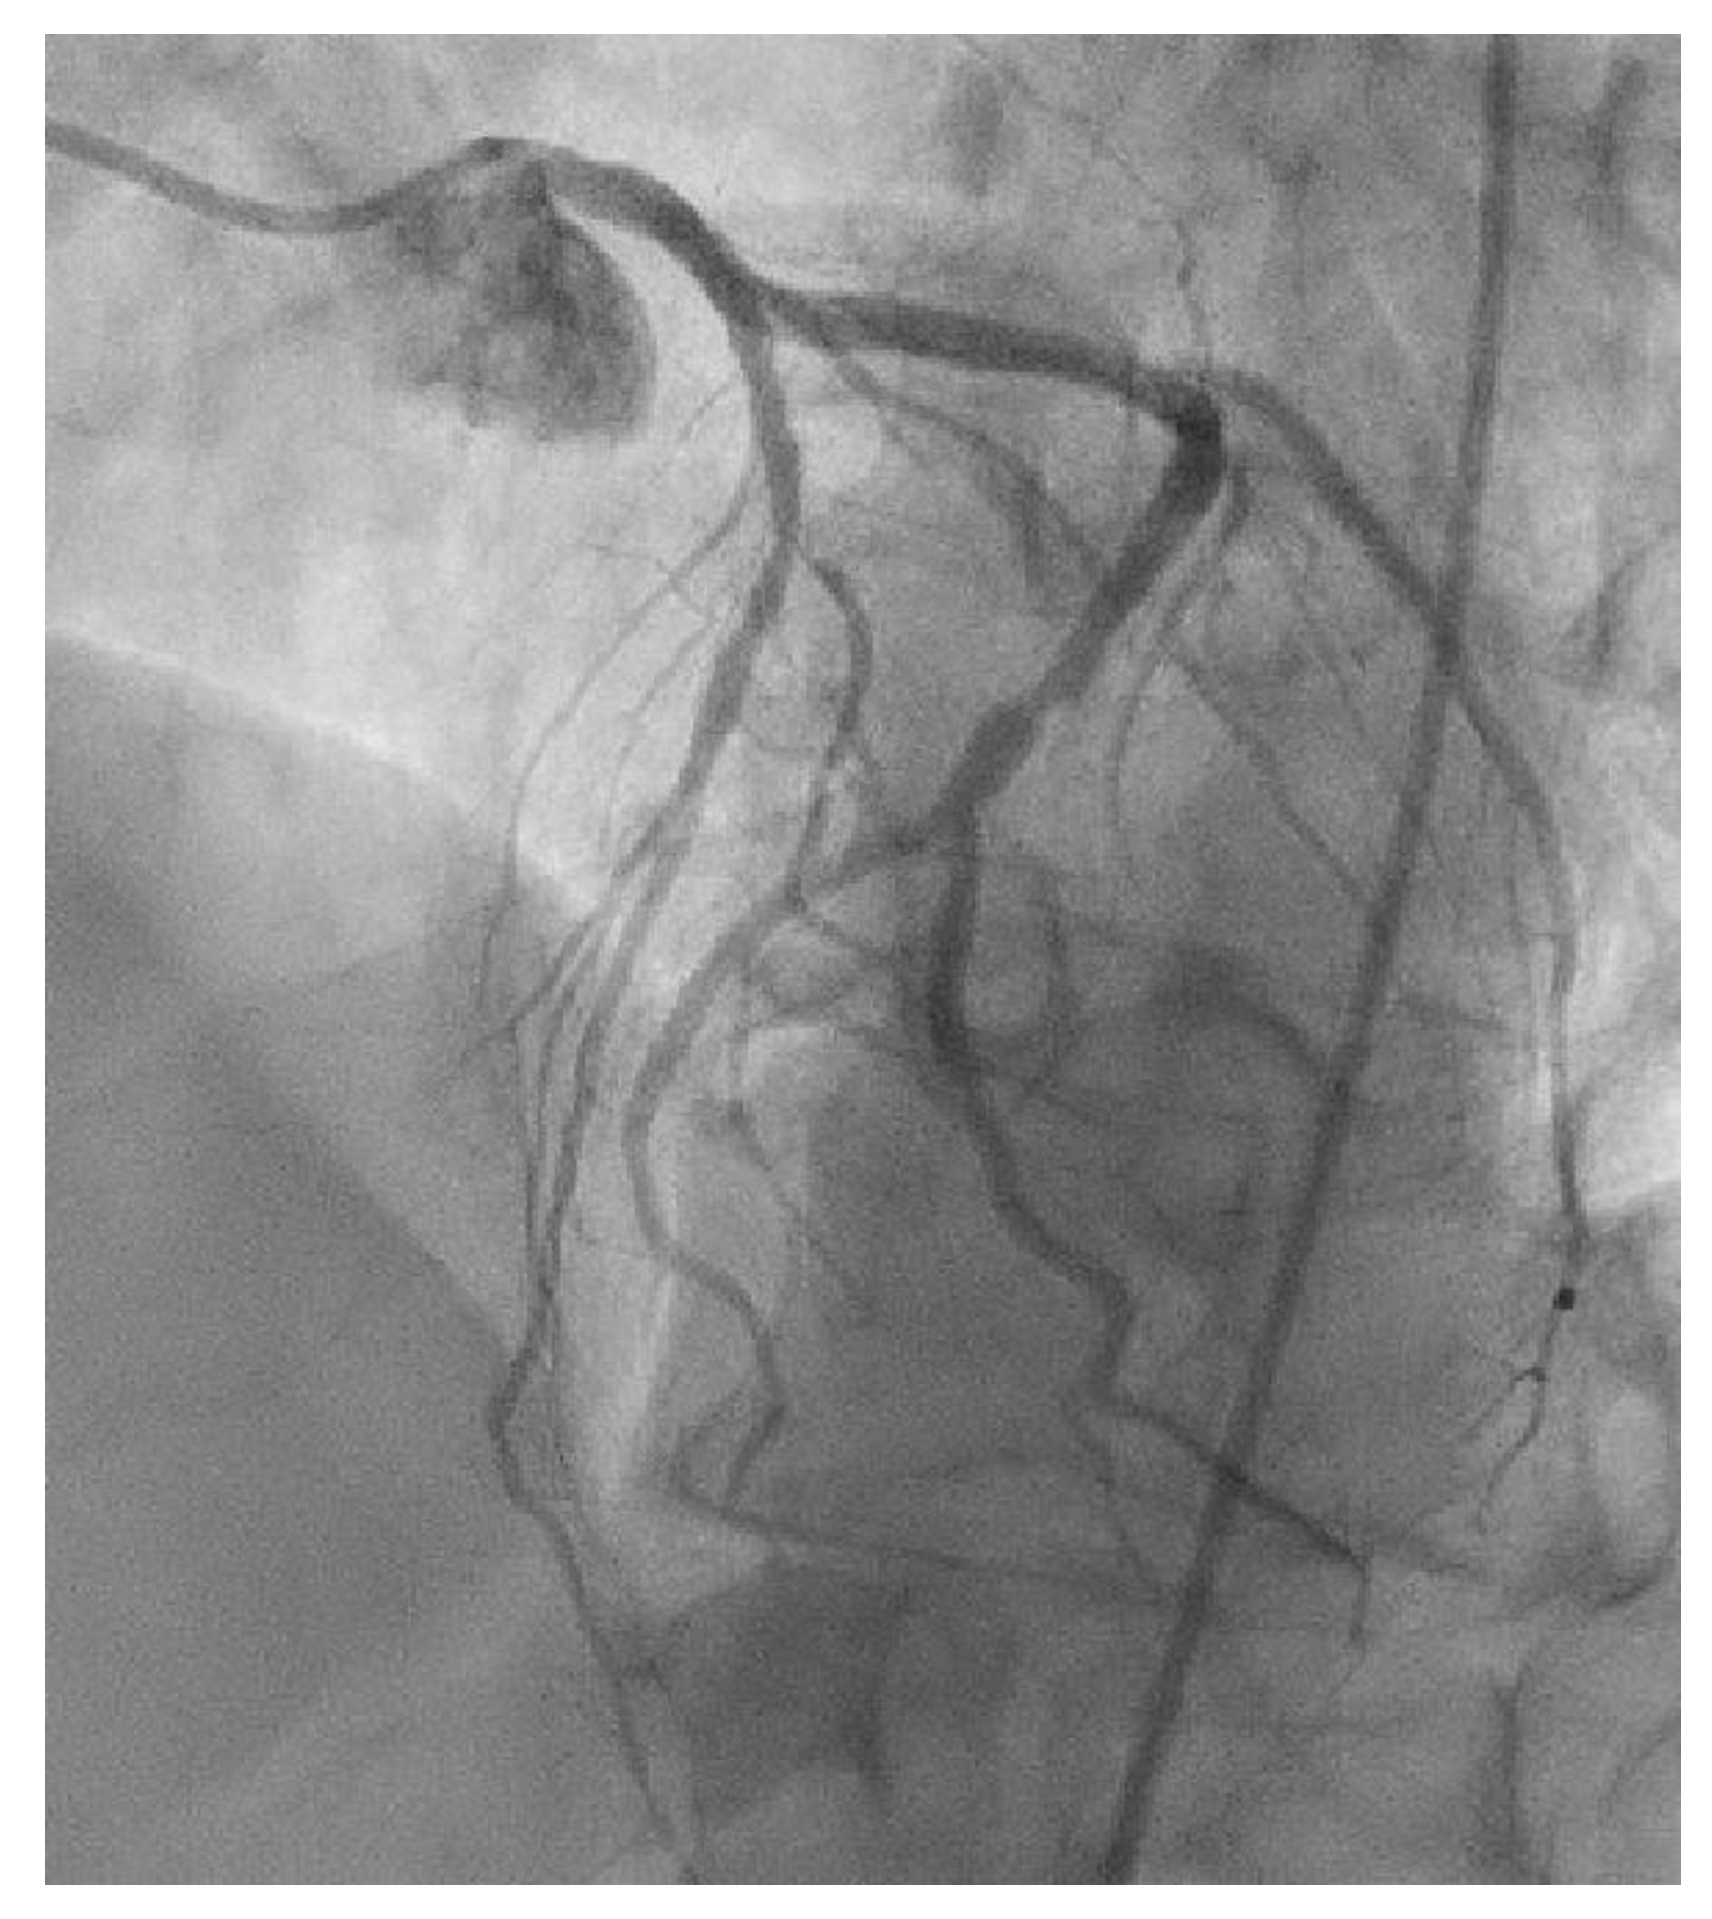

Appendix A.1. Patient A. Male, 46 Years

Appendix A.2. Patient B. Male, 45 Years